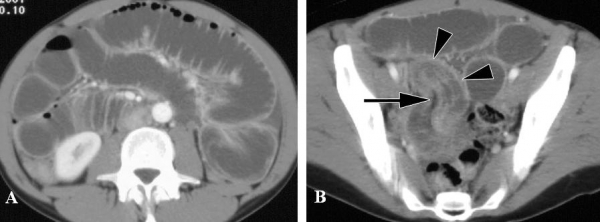

Hình 12: A, CT cản quang thì động mạch, hình ảnh thoát thuốc cản quang từ cổ túi thừa Meckel ở đoạn xa hồi tràng (mũi tên). B, Thì trễ, hình ảnh tăng đậm độ và lẫn thuốc cản quang trong lòng túi thừa do xuất huyết ( mũi tên).

( Danzer, P. Gervaz, A. Platon, P.-A. Poletti (2003). Bleeding Meckel’s diverticulum diagnosis: an unusual indication for computed tomography. Abdominal Imaging 28:632)

Hình 13: Xuất huyết tiêu hóa do niêm mạc dạ dày lạc chỗ trong túi thừa Meckel ở bệnh nhân nam 22 tuổi. A, CT không cản quang. B, thuốc cản quang thoát vào lòng túi thừa Meckel (Alexandra Platon, Pascal Gervaz et al (2010). Computed tomography of complicated Meckel’s diverticulum in adults: a pictorial review. Insights Imaging 1:59)